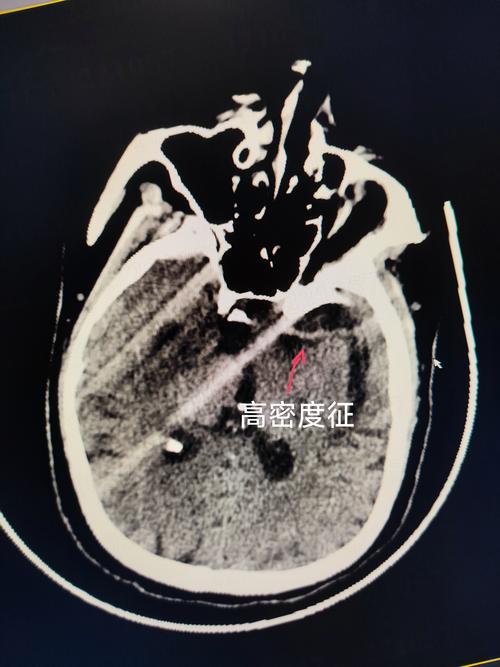

脑梗

- 脑梗:全称是“脑梗死”或“缺血性脑卒中”,是指因脑部血管阻塞,导致血液供应中断,使脑组织缺血、缺氧而发生坏死,造成神经功能缺损。

- 常见原因:最常见的原因是血栓栓塞,即身体其他部位(尤其是心脏或颈部动脉)的血栓脱落,随血流堵塞了脑部的动脉。